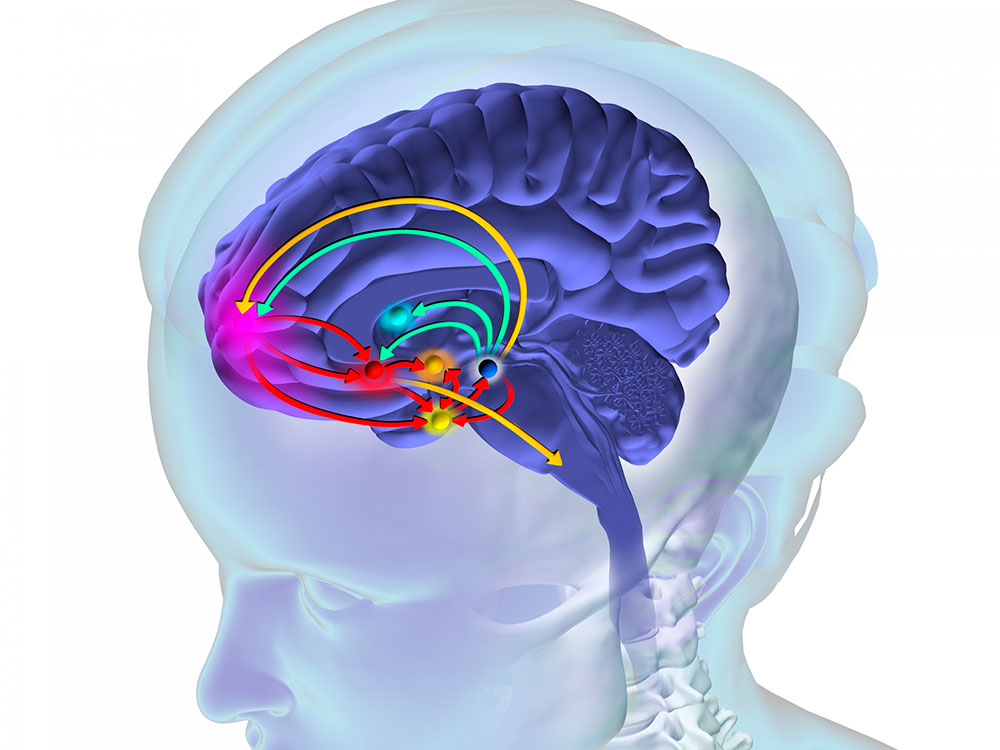

✨ ¿Cómo afecto la drogadicción a la salud mental?

🌿 Drogadicción y Salud Mental

La drogadicción es un problema complejo que afecta a millones de personas en todo el mundo. A continuación, te presentamos información y recursos sobre la drogadicción y cómo afecta a la salud mental.

La drogadicción es una enfermedad crónica que se caracteriza por el uso compulsivo de sustancias psicoactivas, a pesar de las consecuencias negativas para la salud, las relaciones y la vida en general.

🧠 Efectos en la salud mental